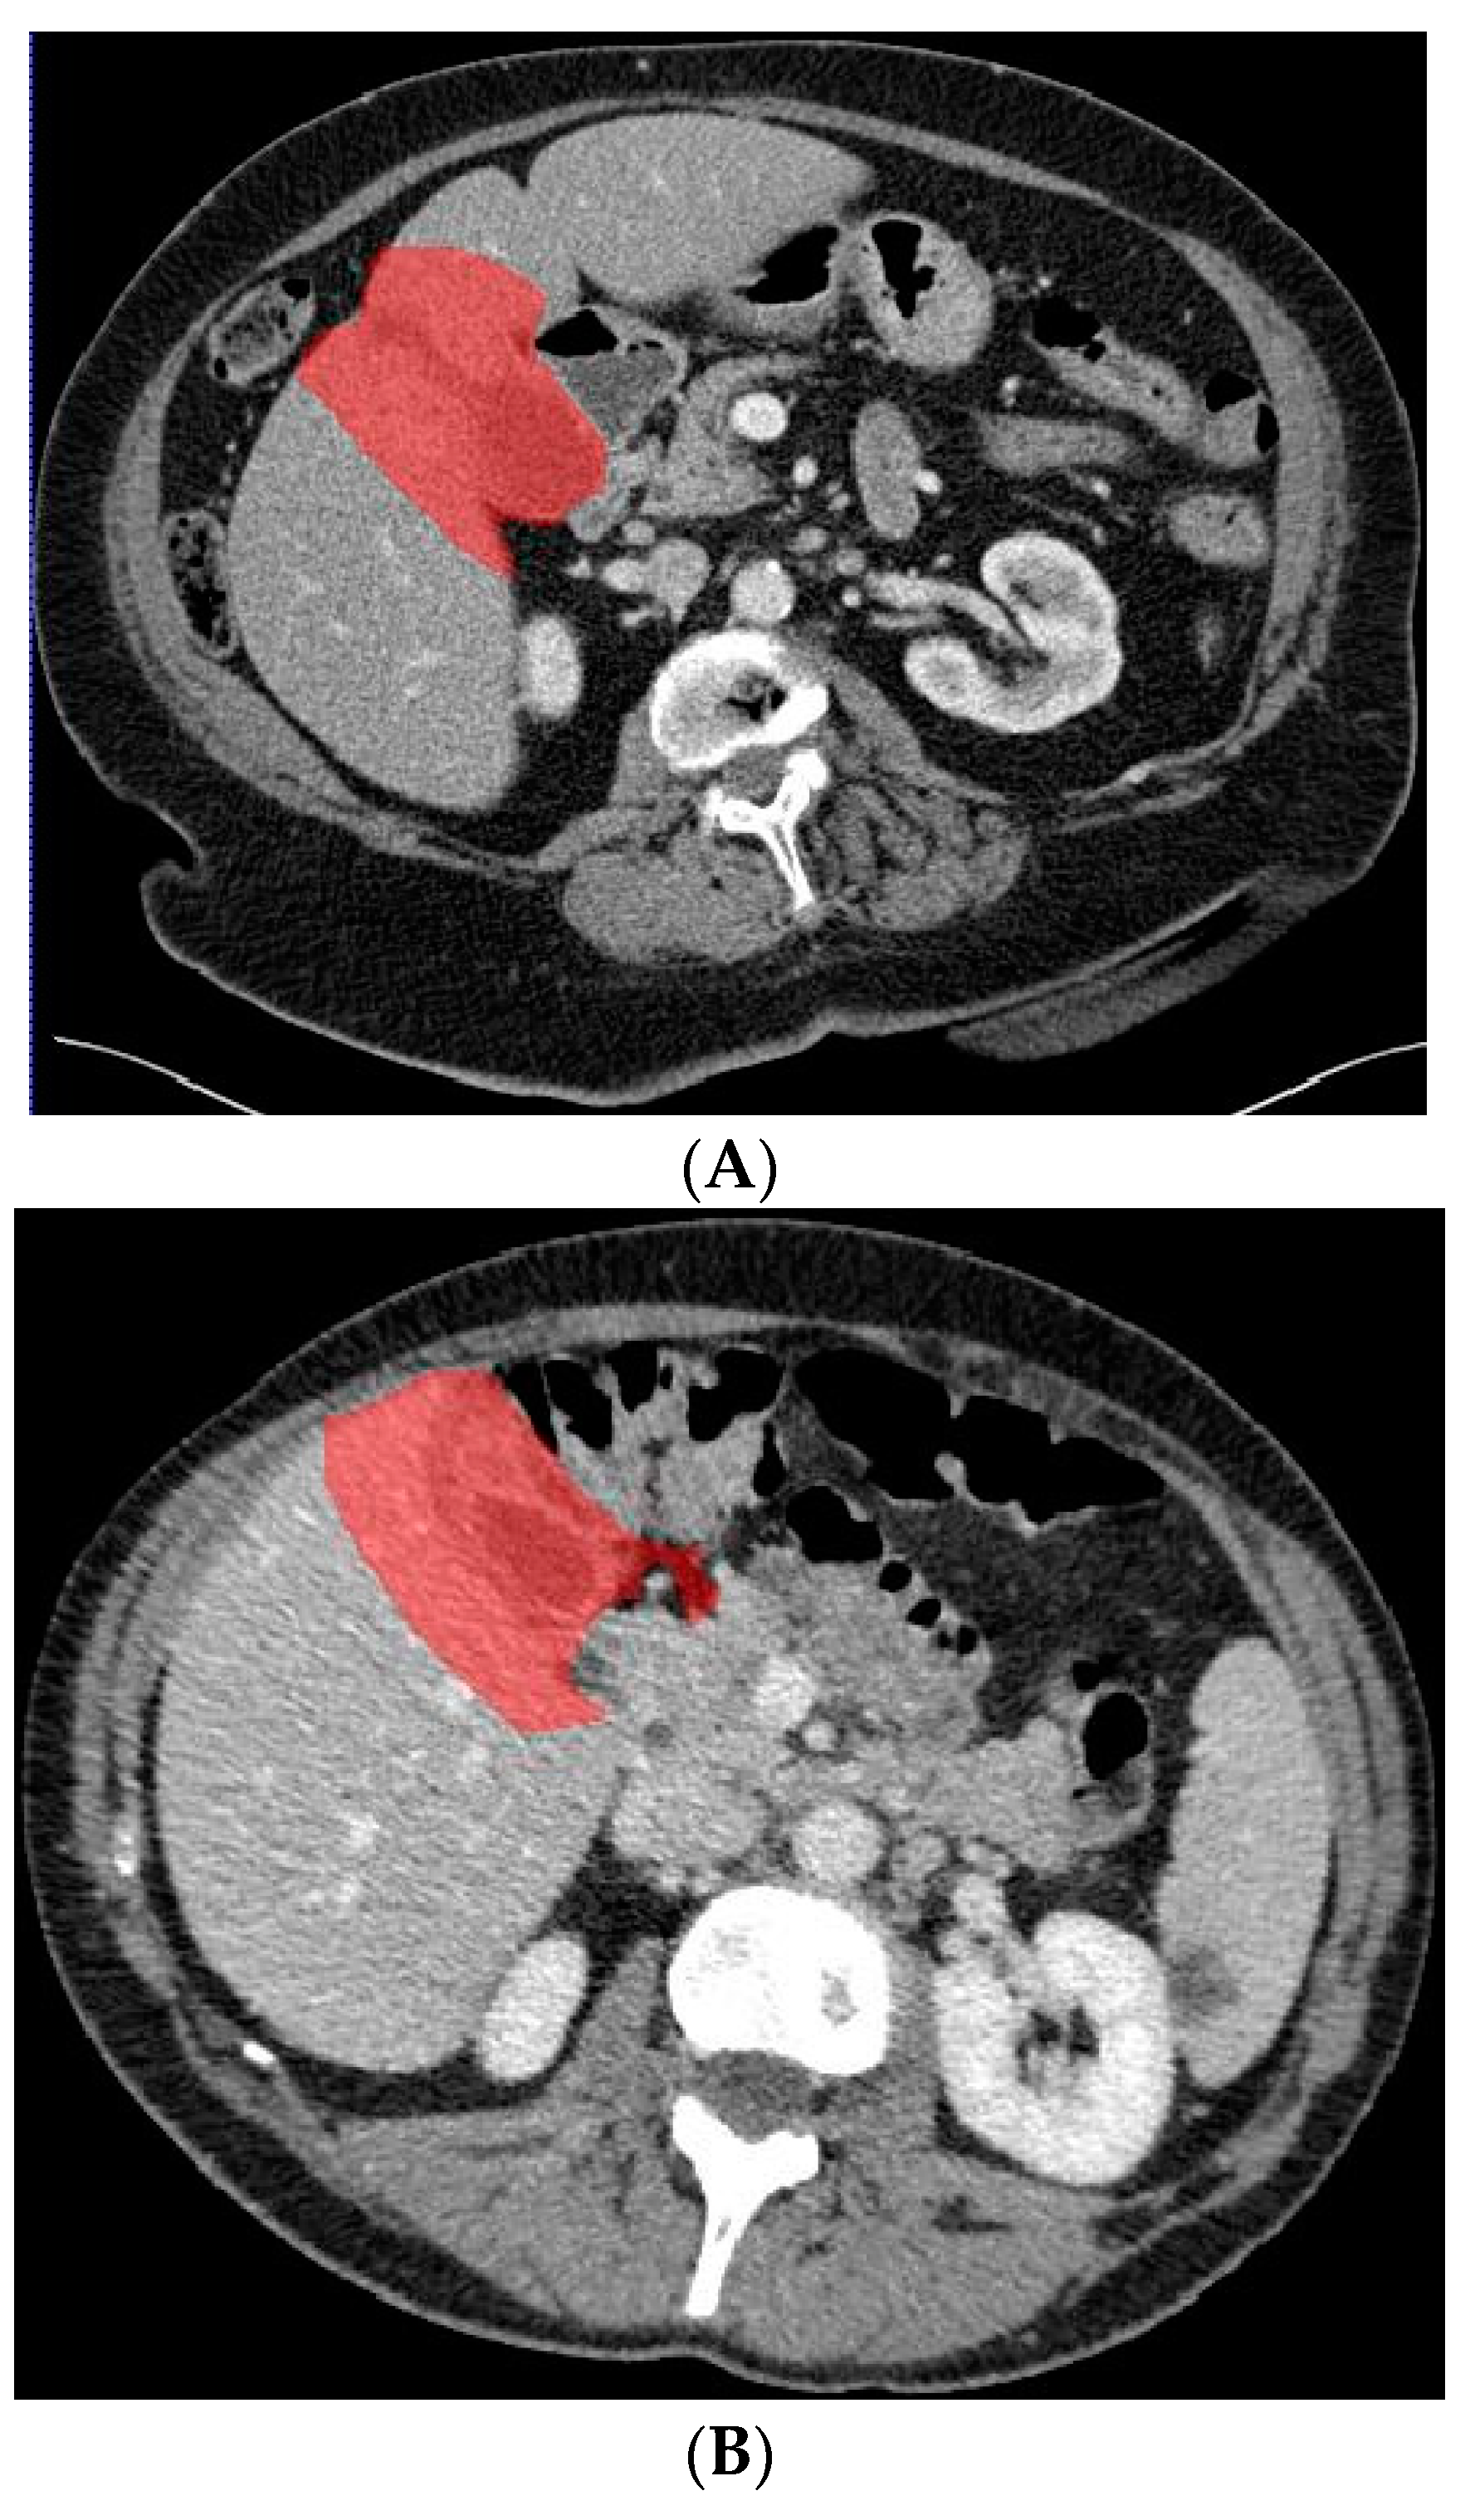

2.3. Deep Learning Model Based on Gallbladder and Liver Parenchyma

In a previous study, the suspicion of invasion of adjacent liver parenchyma was observed to be positively related to GBC [5]. Therefore, in addition to using only the gallbladder on CT images when training the deep learning model, a separate analysis was performed to investigate whether the combination of the gallbladder and adjacent liver parenchyma could increase the performance of the deep learning model when differentiating between GBC and benign gallbladder disease. The segmentation of a 2 cm rim of liver parenchyma adjacent to the gallbladder was automatically generated and adjusted by an experienced abdominal radiologist if necessary. The adjacent liver parenchyma was combined with the segmented gallbladder as training data for the deep learning model. Figure 4 shows examples of input CT images with segmentation of both the gallbladder and 2 cm of adjacent liver parenchyma. The deep learning model based on the combination of the gallbladder and adjacent liver parenchyma was trained and tested by the same methodology as described for the model solely based on the gallbladder.